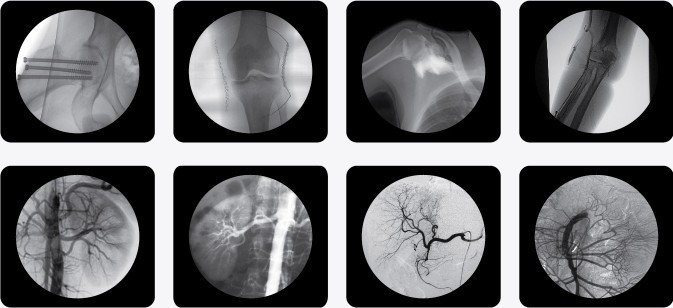

PLX7000B高頻移動式C型臂X射線機(C型臂X光機)

一、C型臂X光機PLX7000B的用途

廣泛應用于 介入科、骨科、外科、矯形外科、泌尿外科、脊柱外科、腹部外科、疼痛科、心臟科、消化科、婦科及手術室等。

三、C型臂X光機PLX7000B數(shù)字高清影像,支持您做出精確診斷

·數(shù)字化高頻發(fā)生器,采用微焦點,確保精準的射線劑量控制,滿足您的多種復雜臨床診治要求。

·球館大熱容設計,保證設備持久工作能力,伴隨您一同應對各種復雜手術。

·全數(shù)字化百萬像素影像采集系統(tǒng),優(yōu)化設計和配置,為您提供高分辨率、高灰階圖像,支持您做出精確診斷。